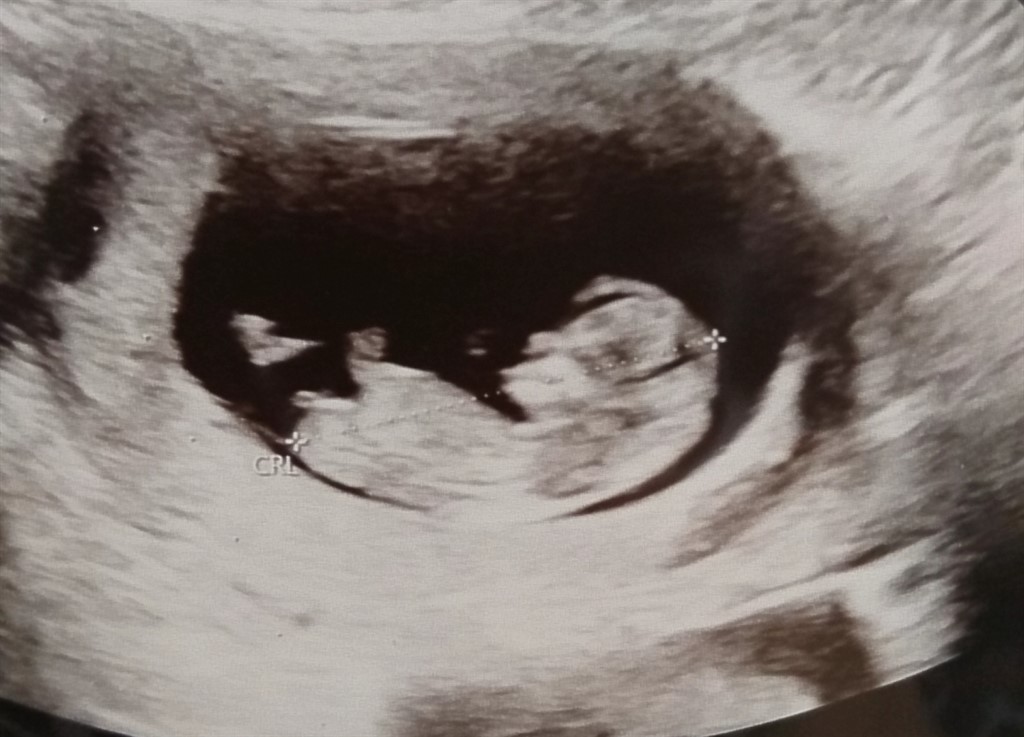

Er der nogen der vil give et gæt på hvad hvad jeg gemmer på i hulen?  vi får svar inden forhåbentlig ret mange dage, om hvad vi har fået brygget sammen.. Er simpelthen ved at gå til af spænding

Efter nub teori ligner det en pige da den går lige ud, ligesom ved vores lille pige